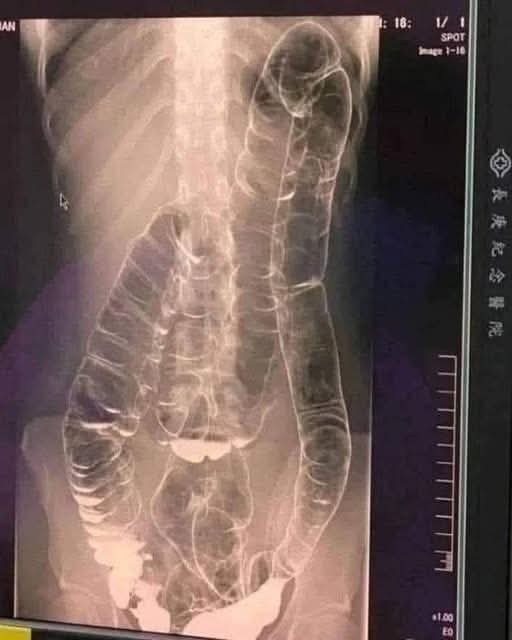

Constipation may seem like a minor issue, but ignoring it can lead to serious health risks. One young woman, after two weeks without a bowel movement, ended up with a dangerously swollen colon that nearly impacted her heart—prompting emergency care. Doctors warned that waiting longer could’ve been fatal.

Constipation might seem like a harmless inconvenience, but when left unaddressed, it can develop into a serious and even life-threatening condition. A shocking real-life case serves as a stark reminder of the dangers of chronic constipation and why it should never be ignored. A young woman suffering from years of digestive issues experienced a severe decline in her health after going more than two weeks without a bowel movement.

- Colonic distension (a stretched colon that loses function)